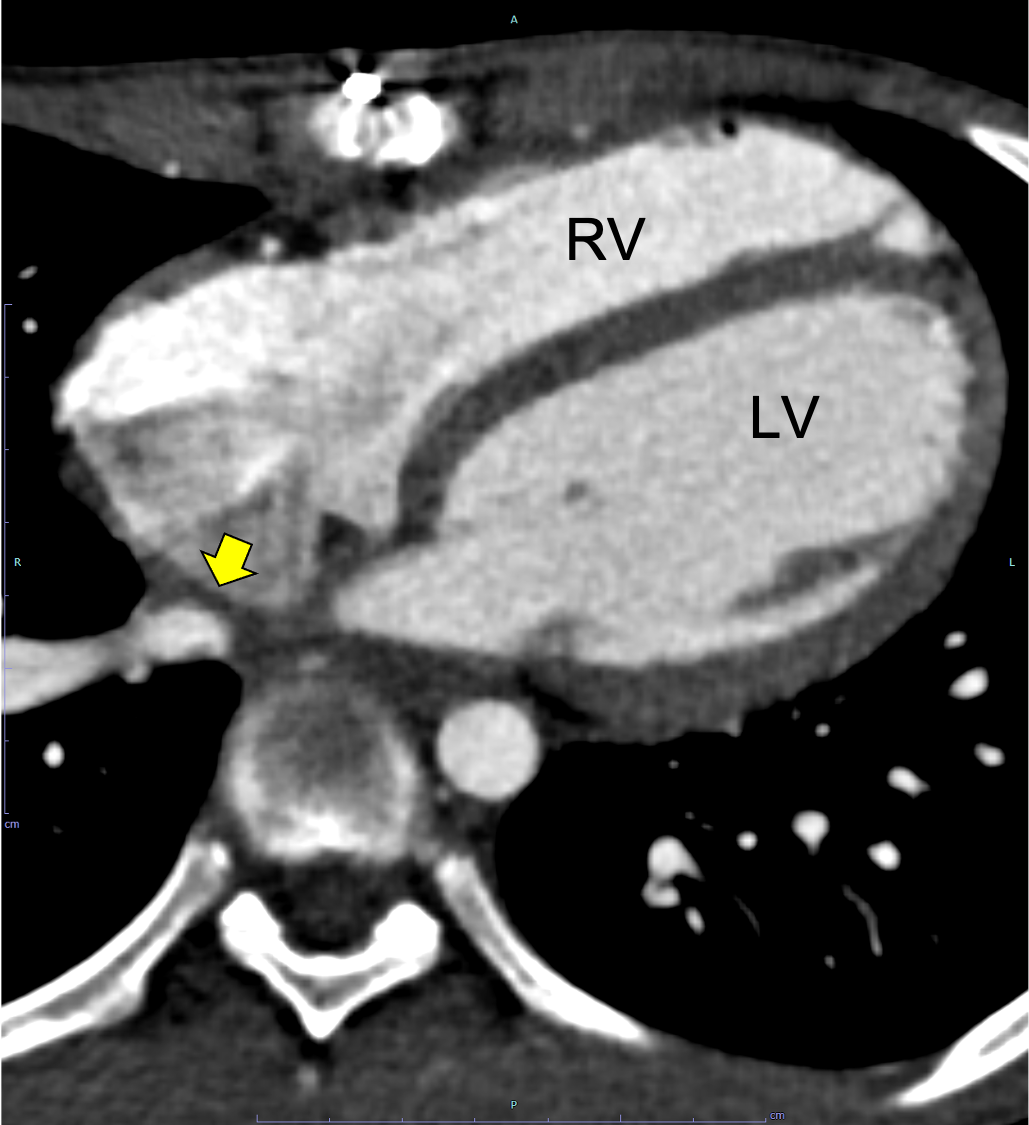

図2.心電図同期造影CT水平断(動脈相、心尖部レベル)

右室の拡大を認める。RV: 右心室、LV: 左心室